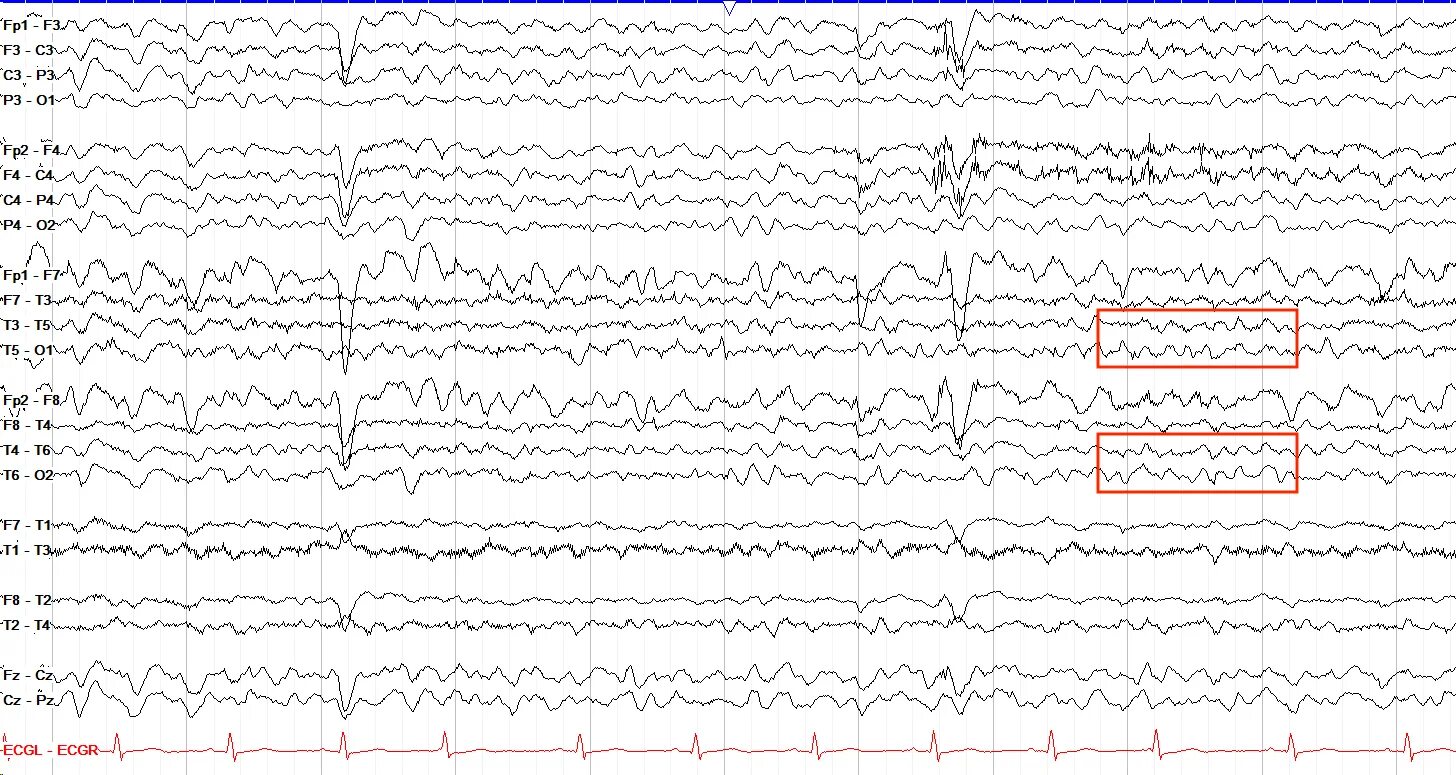

Эпилепсия изменения на ээг